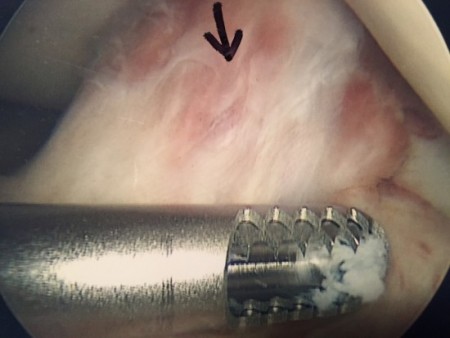

- Why do tools matter? Most of my clients with arthrofibrosis, myself included, have had failed surgeries during which scar tissue was “cleaned out” using a tool called a shaver (also called a debrider).

- While this is an important arthroscopic tool, it is not well suited to address arthrofibrosis. It isn’t precise, and by virtue of shredding scar tissue, it causes bleeding–sometimes profuse bleeding. My two pre-Steadman Clinic surgeries required use of a tourniquet to stop bleeding. Earlier, I mentioned bleeding can lead to scar tissue formation, so by using a shaver/debrider, the very environment that resulted in scarring to begin with is recreated.

- If you’ve had a previous failed surgery, have a look at your surgical images and see if you notice a shaver in the photo.